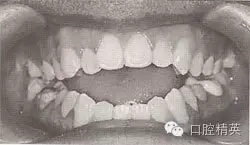

開頜畸形是上下牙弓及頜骨在垂直方向上的發(fā)育異常,其臨床表現(xiàn)是上下頜部分牙在正中頜位及下頜功能運動時在垂直方向上無頜接觸(圖9-37),嚴重者只有個別后牙有接觸。其形成機制為前段牙、牙槽或頜骨高度發(fā)育不足,后段牙、牙槽或頜骨高度發(fā)育過度,或兩者兼有。有學者通過三維頭影測量技術對恒牙早期前牙開頜患者進行測量研究后得出,開頜不僅為高度的不調畸形,而且是長二寬、高三向的不調畸形,開頜患者面部寬度顯著減小,上下牙弓明顯狹窄。開頜畸形可發(fā)生在乳牙列、混合牙列和恒牙列,發(fā)生在乳牙列和混合牙列期的開頜畸形的矯治在預防性矯治章節(jié)中已述及,這里重點介紹恒牙列開頜畸形的矯治。

圖9-37 前牙開頜(牙齒有縫)